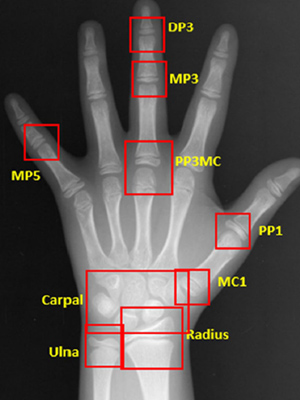

소아청소년기의 정상적인 성장 여부 판단을 위해

손뼈 엑스레이를 분석하여

높은 정확도의 골연령 판독 결과를 제시합니다.